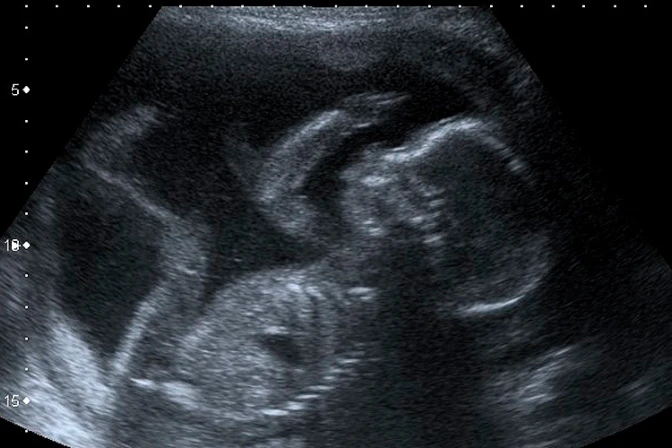

Los obispos de Bolivia manifestaron su preocupación por "el avance de la cultura de la muerte y el descarte" que podría traer consigo la reforma del Código Penal, que busca abrir la posibilidad del aborto hasta las 8 semanas de embarazo para las mujeres pobres y estudiantes.

Las condiciones para acceder al aborto serían declaran no tener recursos suficientes, estar en situación de calle, viven en pobreza extrema, tener más de tres hijos, entre otras.